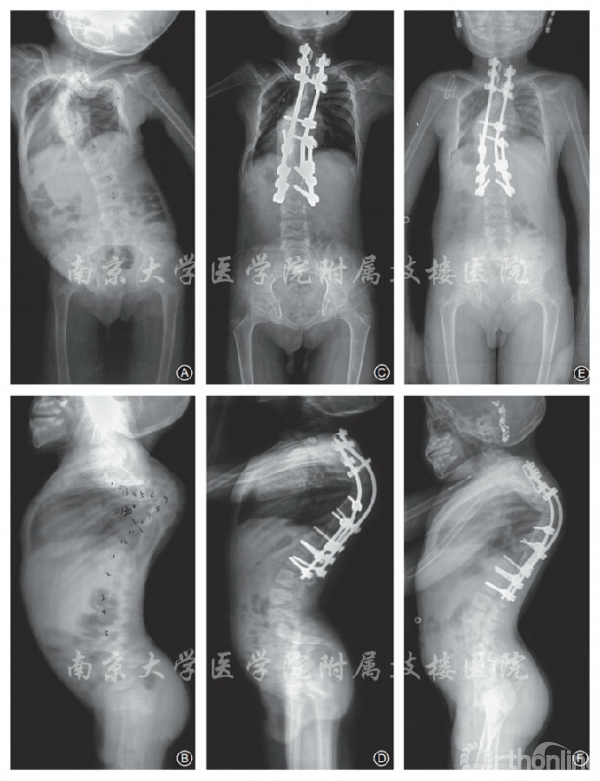

冠状面及矢状面均得到矫形(图4)。术后即刻冠状面主弯 Cobb 角为39.3°±15.1°(15.0°〜55.0°),矫正率为50.3%±20.5%(14.5%〜85.0%);术后即刻后凸Cobb角为41.3°±16.6°(20.0°〜72.0°),矫正率为39.0%±13.0%(20.8%〜57.9%)。末次随访时,冠状面Cobb角为38.1°±11.8°(18.0°〜56.0°)矫正丢失率为6.1%±7.5%(1.8%〜20.0%);后凸Cobb角为39.4°±16.2°(22.0°~69.0°),矫正丢失率为 3.1 %±4.2%(5.2~10.0%,图5)。

图4 男,6岁,先天性脊柱角状侧后凸畸形伴双下肢不全瘫 A,B 术前站立位全脊柱正侧位X线片示上胸左弯84°,胸后凸130° C,D 行后路矫形内固定+脊髓内移术后站立位全脊柱正侧位X线片示胸左弯32°,胸后凸40° E,F 术后1年站立位全脊柱正侧位X线片示胸左弯34°,胸后凸41°